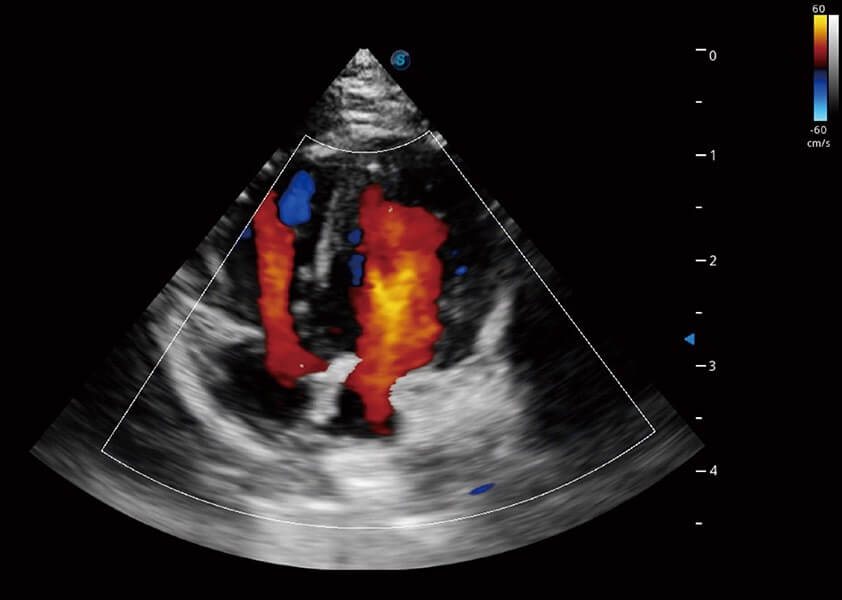

ProPet 60 作为一款高端台式动物超声设备,为动物医生的日常诊断提供了一系列贴合动物临床需求、解决临床实际问题的高级成像功能。凭借全系列高清探头,满足医生对腹部、心脏、生殖、浅表、肌骨等成像的所有需求,切实帮助您提升检查效率,提高诊断信心。

ProPet 60 尊享版

兽用彩色多普勒超声诊断系统